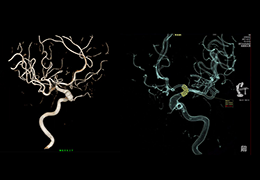

ANYTHINK 经导管主动脉瓣膜置换术分析系统